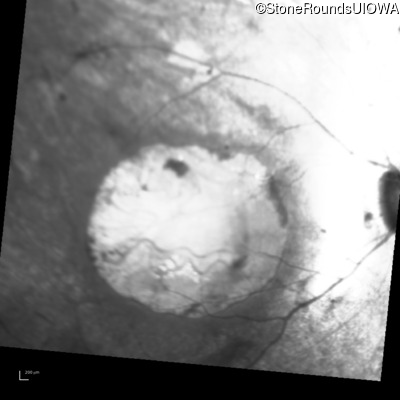

Infrared Fundus Photograph - Left - 20/100 -1

Exemplar